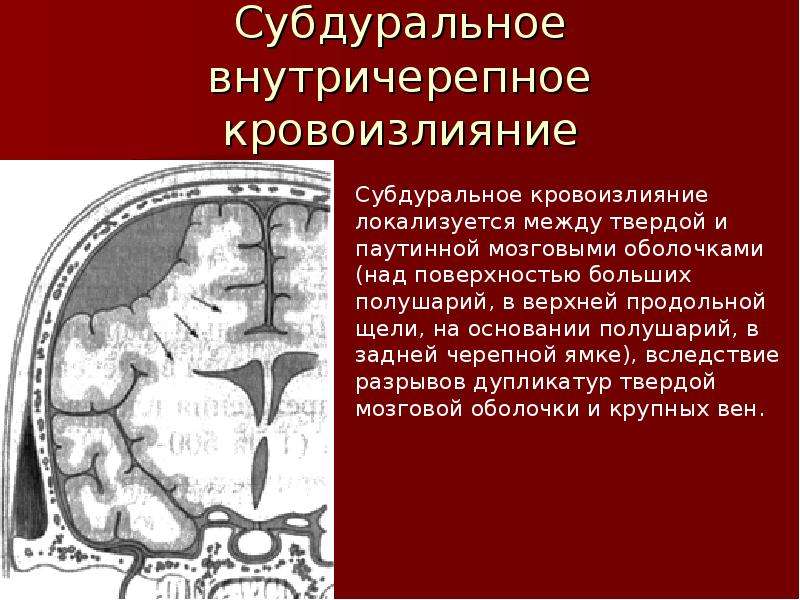

Внутричерепные кровоизлияния у новорожденных презентация - 92 фото